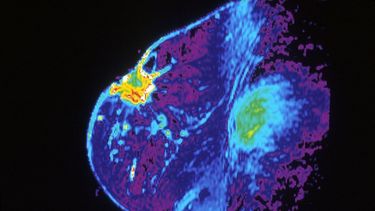

Cambios en el tejido mamario aumentan el riesgo de cáncer

El equipo internacional dirigido por James Lorens, profesor de Biomedicina en la Universidad de Bergen, Noruega, observó células de 56 mujeres y descubrió que, a medida que aumenta la edad del sujeto y se acumulan células progenitoras multipotentes en la capa epitelial del tejido mamario